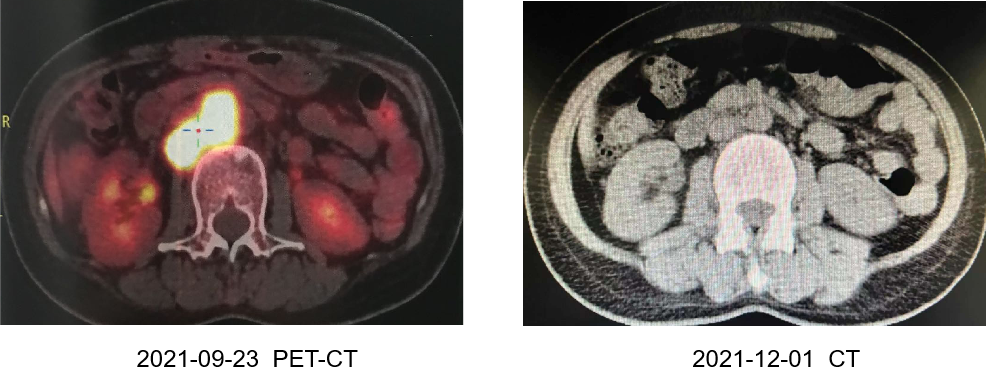

• PET-CT(2021-12-01 vs 2021-09-23):淋巴结明显缩小,部分缓解(PR)。

①左侧锁骨上窝(包括颈部IV区):多发低回声淋巴结,较大者直径变化1.05cm vs 3.13cm。

②左侧腋下:多发低回声淋巴结,较大者直径变化1.51cm vs 2.05cm。

• 全腹PET-CT(2021-12-01 vs 2021-09-23):腹膜后淋巴结明显缩小,PR,继续原方案治疗。

8

直乙交界处病灶明显缩小

9

腹膜后淋巴结明显缩小